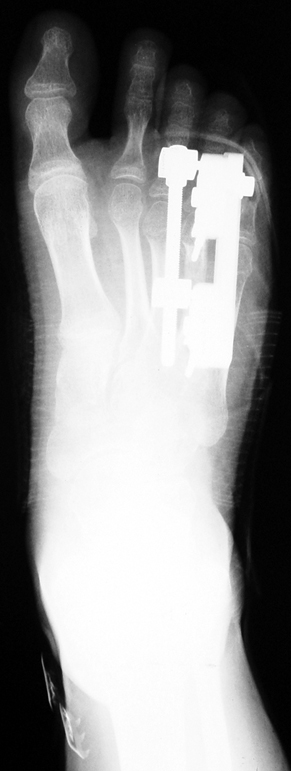

Doğuştan metakarp ve metatars kısalıklarının redavisi için pek çok teknik tanımlanmakla birlikte en çok akut uzatma sonrası kemik uçlarına greft konması ve distraksiyon osteogenezi (kallotasis) kullanılmaktadır. 1 cm.den daha fazla uzatma gereken olgularda kallotasis yöntemi önerilmektedir. Kliniğimizde de metatars ve metakarp uzatma için unilateral eksternal fiksatör ve sirküler eksternal fiksatör yardımıyla distraksiyon osteogenezi yöntemi tercih edilmektedir.